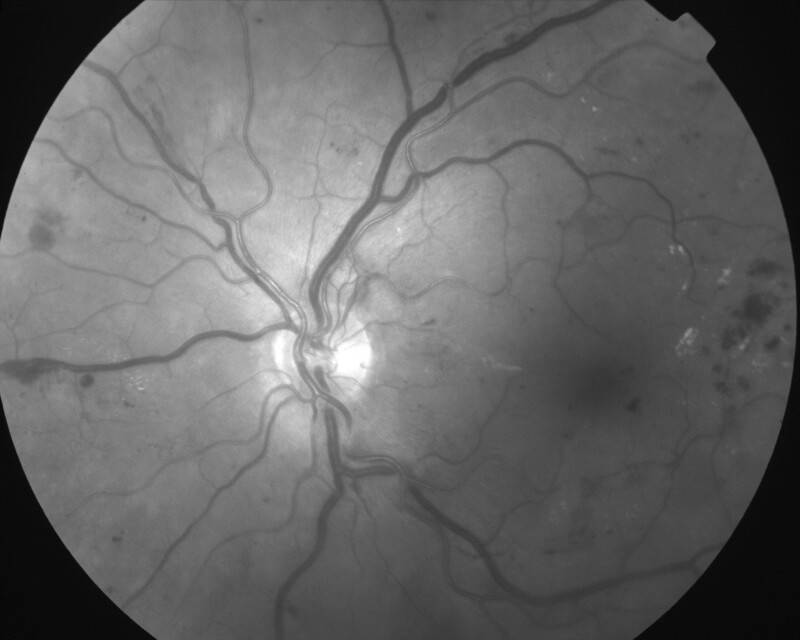

RETINOPATHIE DIABETIQUE PROLIFERANTE